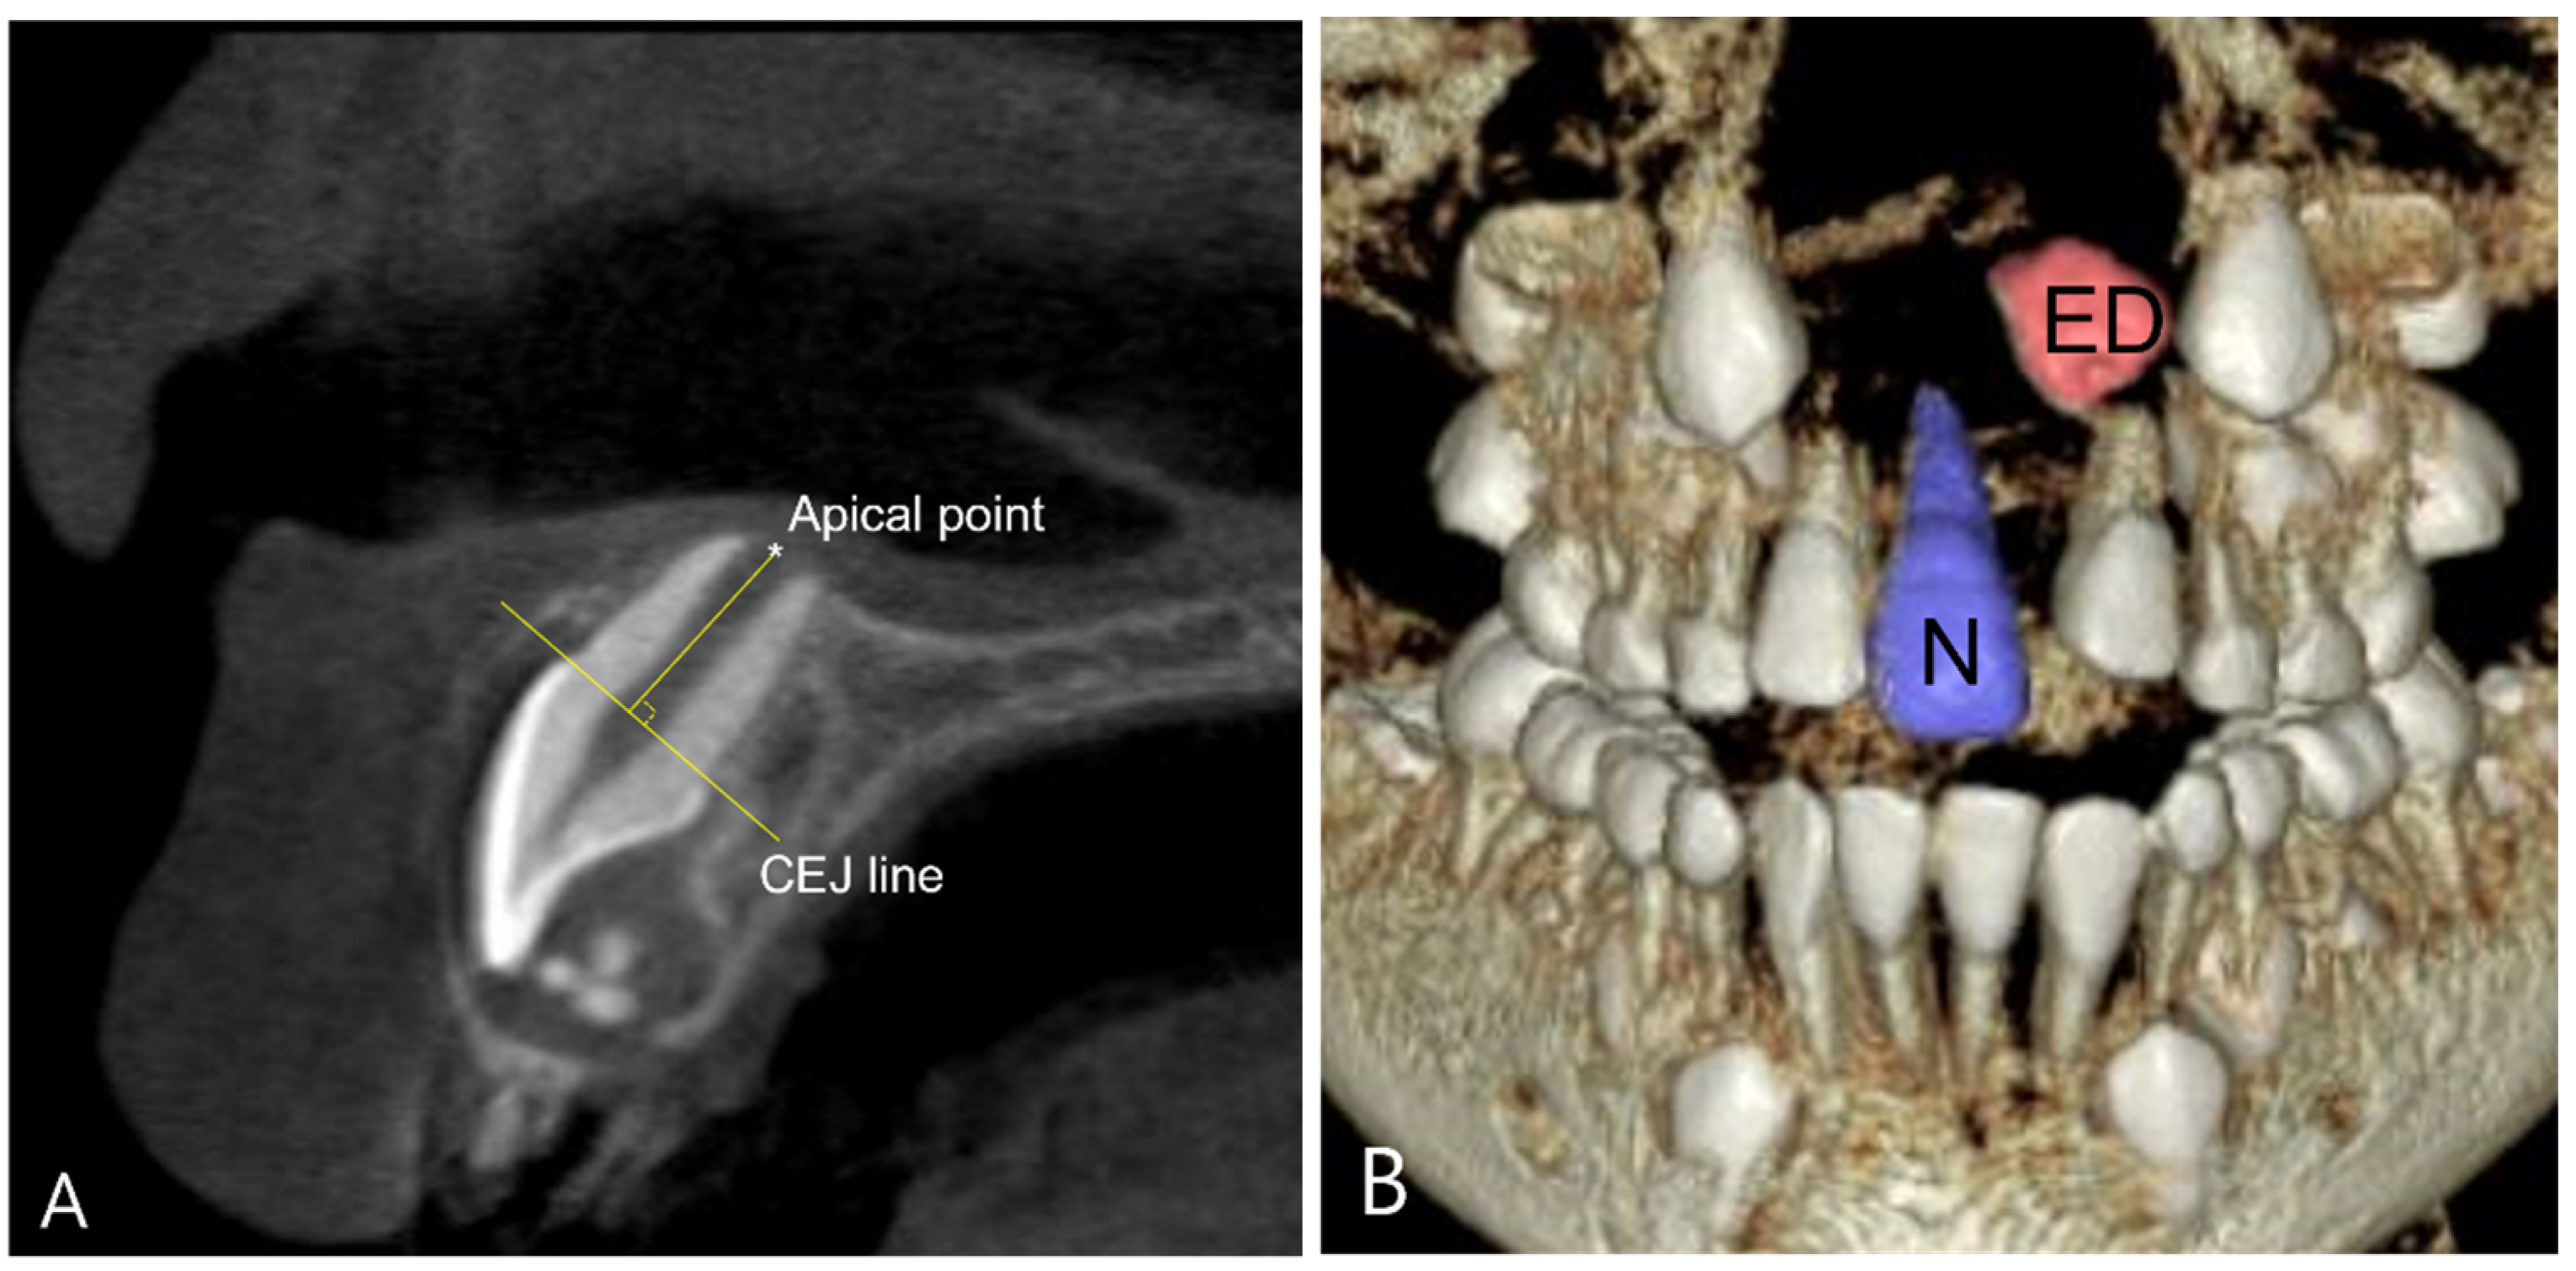

2.4. CBCT Measurement